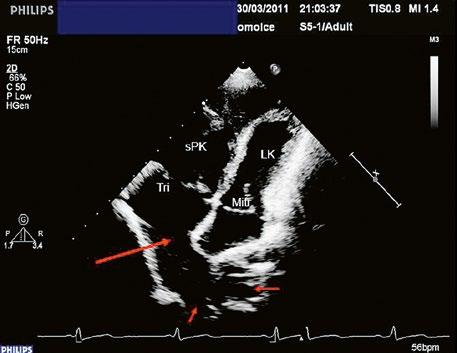

Obr. 45.15 Přechodná forma atrioventrikulárního septálního defektu, TEE, čtyřdutinová projekce. V dolní části síňového septa je mezi pravou síní (PS) a levou síní (LS) velká komunikace typu ostium primum (označená šipkou), původní komorová složka defektu (označená hvězdičkou) je částečně spontánně uzavřena závěsným aparátem trikuspidální chlopně.